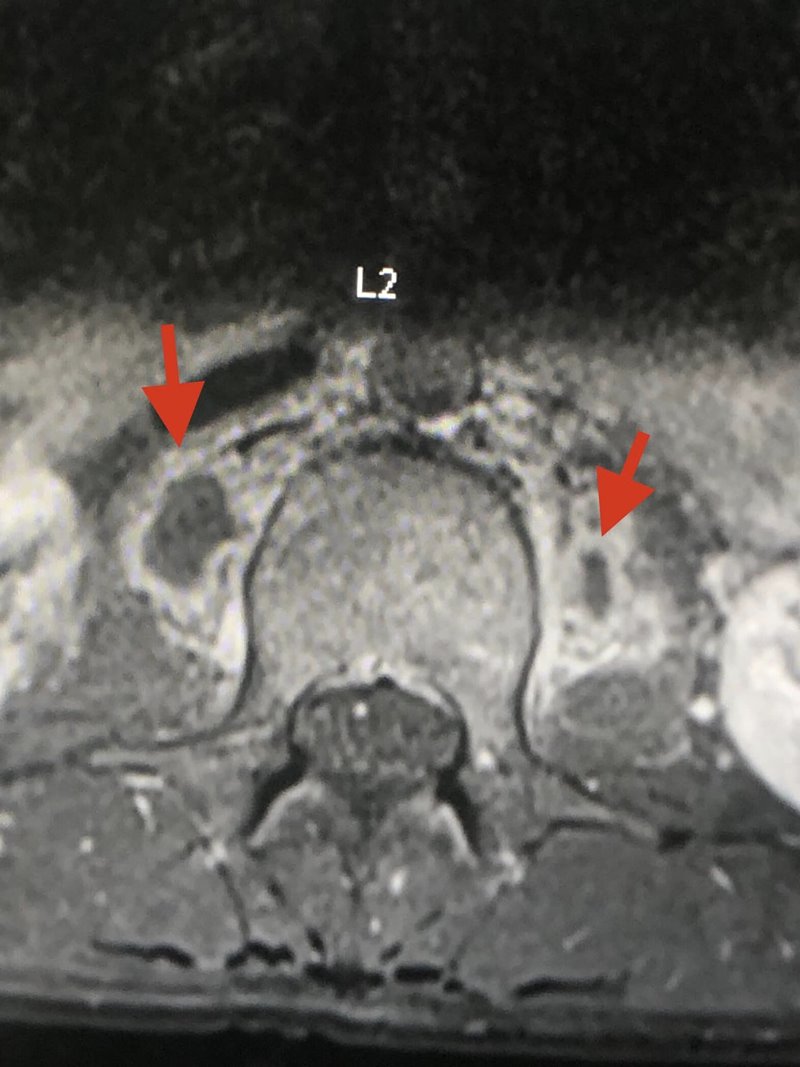

อย่างไรก็ตาม เมื่อลองทำ MRI กระดูกสันหลังส่วนเอว กลับพบความผิดปกติ และมีความเป็นไปได้ที่เธอจะเป็นวัณโรคของกระดูกสันหลังส่วนเอวชิ้นที่ 1 และสงสัยว่าจะมีการอักเสบรอบ ๆ เนื้อเยื่อกระดูกสันหลังส่วนเอวชิ้นที่ 1 และ 2 ร่วมด้วย จึงทำการเจาะเนื้อเยื่อรอบกระดูกสันหลัง ส่งตรวจย้อมเพื่อหาเชื้อวัณโรค และให้ผลลบ จากนั้นก็รอเพาะเชื้อวัณโรค ส่งตรวจพยาธิวิทยา พบว่าเนื้อเยื่อตายและไม่พบมะเร็ง และสรุปได้ว่า เธอเป็นวัณโรคที่กระดูกสันหลัง

ภาพจาก เฟซบุ๊ก หมอมนูญ ลีเชวงวงศ์ FC